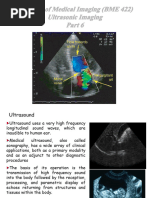

What is Ultrasound Imaging?

 Ultrasound imaging, also called ultrasound scanning

or sonography, involves exposing part of the body to

high-frequency sound waves to produce pictures of the

inside of the body.

 ultrasound images are captured in real-time, they can

show the structure and movement of the body's

internal organs, as well as blood flowing through

blood vessels.